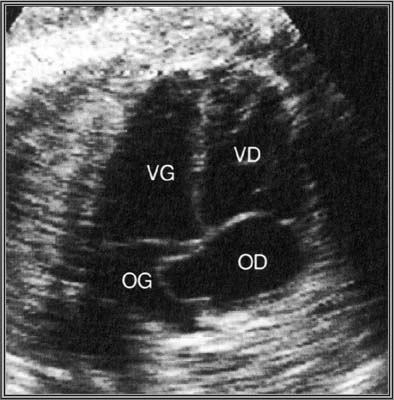

2. Communications inter-ventriculaires

Déhiscences de la cloison inter-ventriculaire.

Echocardiographie bidimensionnelle :

Interruption localisée du septum inter-ventriculaire.

L’incidence des quatre cavités est souvent prise à défaut pour le diagnostic des CIV située sous les gros vaisseaux (les plus fréquentes).

Confirmation de la CIV par le doppler couleur.

Le doppler couleur permet de visualiser de petites CIV musculaires situées au centre du septum inter-ventriculaire ou à l’apex du cœur, non visibles en échographie bidimensionnelle.